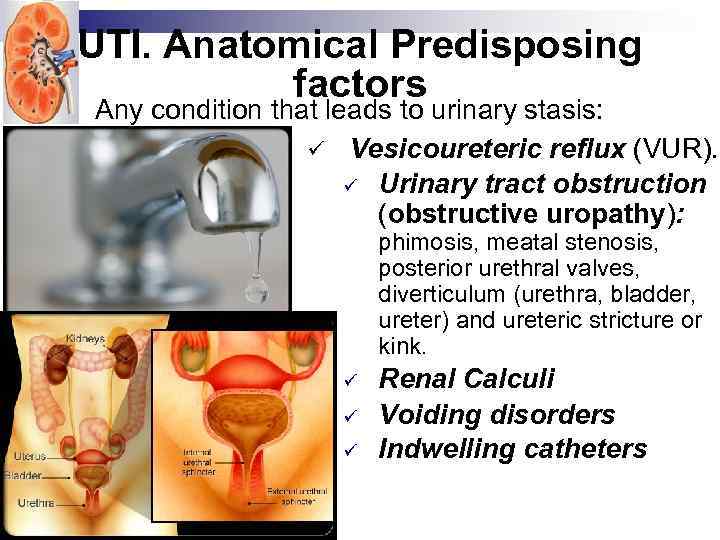

UTI. Anatomical Predisposing factors Any condition that leads to urinary stasis: ü Vesicoureteric reflux (VUR). ü Urinary tract obstruction (obstructive uropathy): phimosis, meatal stenosis, posterior urethral valves, diverticulum (urethra, bladder, ureter) and ureteric stricture or kink. ü ü ü Renal Calculi Voiding disorders Indwelling catheters

UTI. Anatomical Predisposing factors Any condition that leads to urinary stasis: ü Vesicoureteric reflux (VUR). ü Urinary tract obstruction (obstructive uropathy): phimosis, meatal stenosis, posterior urethral valves, diverticulum (urethra, bladder, ureter) and ureteric stricture or kink. ü ü ü Renal Calculi Voiding disorders Indwelling catheters